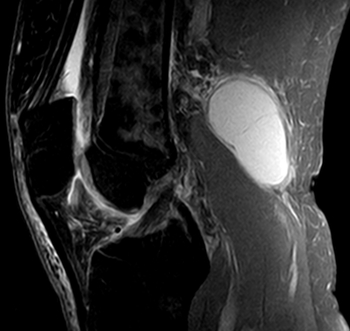

3. 슬와낭종(Popliteal cyst), 베이커씨 낭종(Baker's cyst)

출처-https://upload.wikimedia.org/wikipedia/commons/0/07/Bakerzyste2_MRT_sag.jpg 저작권표시(CC BY-SA3.0)https://creativecommons.org/licenses/by-sa/3.0/

오금 부위에 있는 활액낭에서 발생합니다. 정상에서는 무릎관절과 소통하는 얇은 활액막이지만, 활액막염이 있거나 손상으로 관절액이 증가되면 활액낭으로 흘러들어가 낭종이 형성됩니다. 퇴행성 반월상연골파열, 류마티스 같은 염증성질환과 관련이 있습니다.

베이커 낭종은 무증상인 경우도 흔합니다. 통증이 없으면 치료가 필요치 않고 저절로 없어지기도 합니다.

낭종이 점점 커지거나 통증이 심하다면 무릎관절 내부에 다른 문제가 있는지를 MRI를 통해 살피고 그것에 맞게 치료해야 합니다.